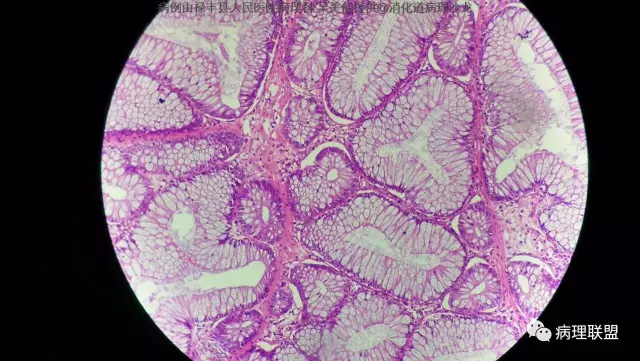

M/50 直肠(P-J息肉VS增生性息肉?)

P-J息肉?增生性息肉?请老师们看看!(病例由禄丰县人民医院病理科 吴美仙提供,致谢!)